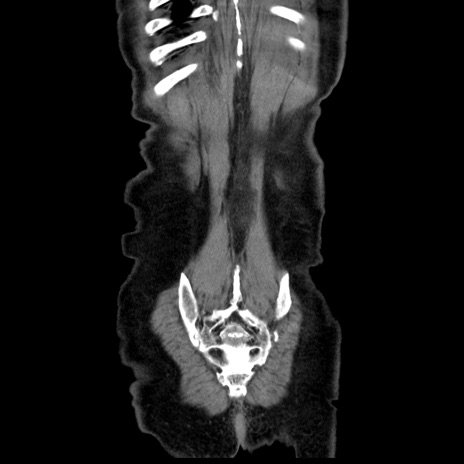

症例30(冠状断像)

【症例】80歳代男性

【主訴】臍周囲痛

【現病歴】約6時間前から臍下部痛が出現。次第に腹部膨隆・背部痛も生じてきたため来院。背部痛の場所は変化しない。

【既往歴】腎盂腎炎

【身体所見】意識清明、BT 36.3℃、BP  131/87mmHg、P 87bpm、SpO2 100%(RA)、臍周囲自発痛・圧痛あり、反跳痛なし、自発痛部位に一致して板状硬あり、腹部膨隆、腸雑音減弱、CVA tenderness両側陰性。

【データ】WBC 19600、CRP 0.33